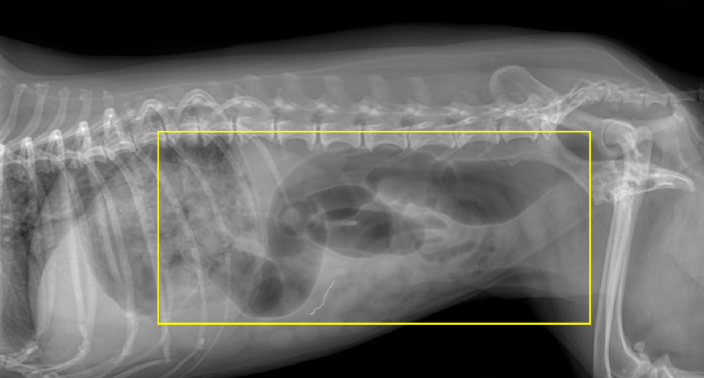

또한, x-ray상에서 위의 내용물이 다량 저류, 소장 확장이 동반된 상태였습니다.

복부 초음파를 통해 복강 내 장기를 평가해본 결과 소장은 가스와 액체가 저류하여 운동성이 감소해 있었으며 췌장 실질이 비대되어 급성 췌장염 소견이 확인되고, 또한 급성 간염이 의심되는 상황이었습니다.

그림 2. 확장된 소장 분절